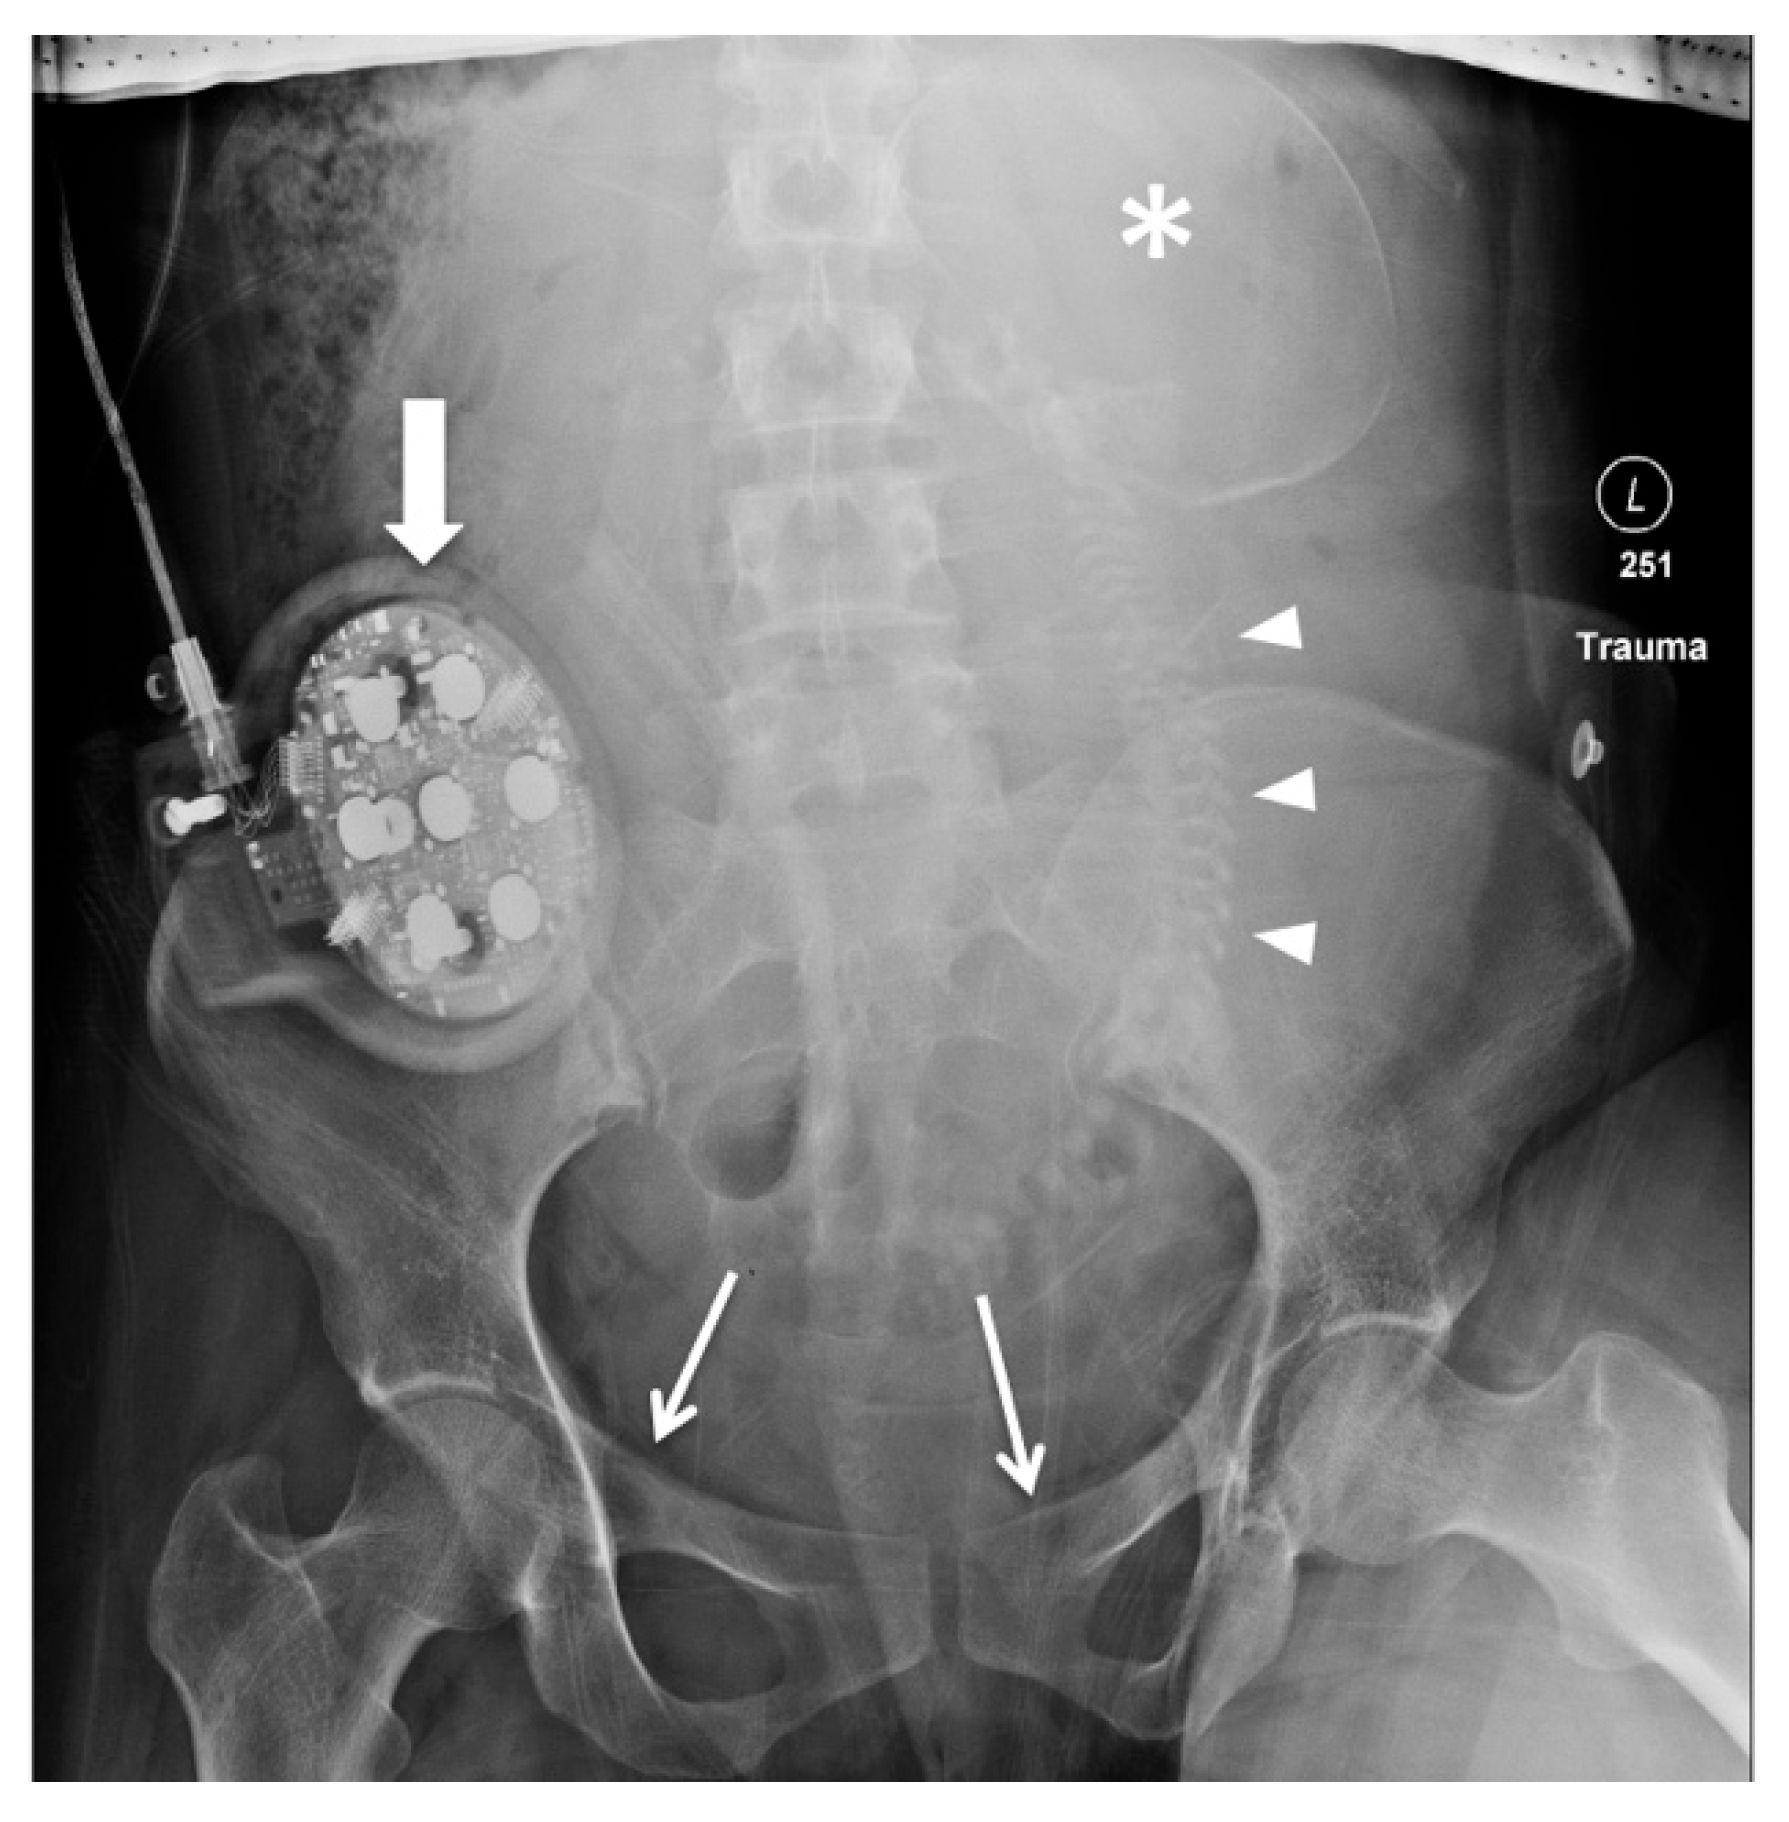

4. Review of Local Presentations